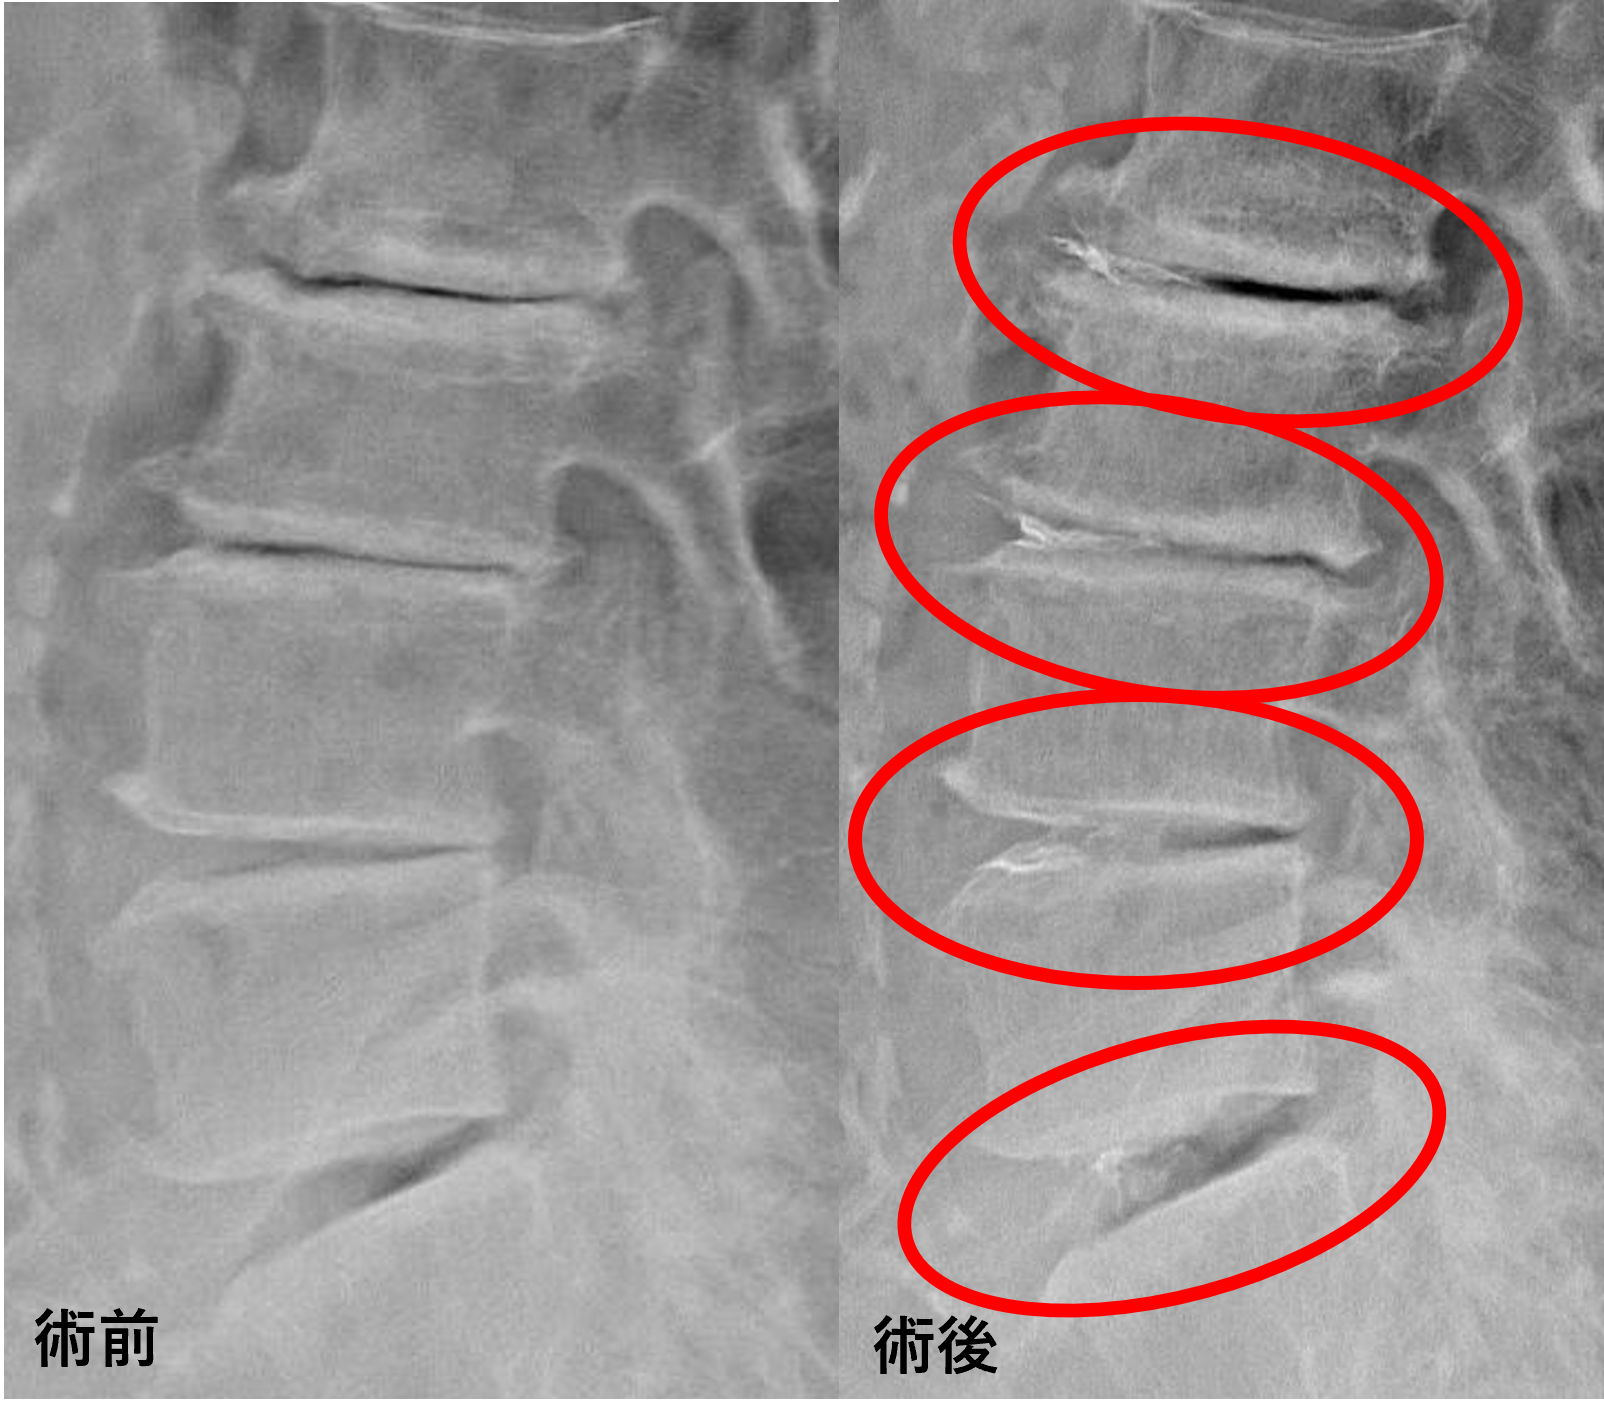

画像及び所見について

- L2/3、3/4、4/5 – 椎間板変性、膨隆

- L5/s – 椎間板変性、椎間板ヘルニア、脊柱管狭窄

以上のことが画像上認められました。

L2/3、3/4、4/5、5/sの椎間板所見による脊柱管の圧排が、症状の原因の可能性が高い。

患者様と相談の元、L2/3、3/4、4/5、5/sにセルゲル法を施行